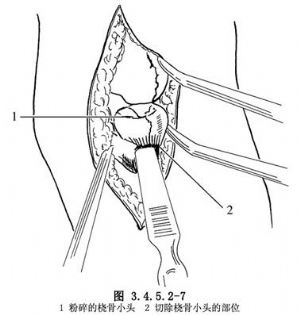

(3)縱行切開關節囊,顯露橈骨頭,可見橈骨頭已呈粉碎狀。清除關節內積血,仔細檢查骨折情況。用紗布保護關節腔,防止骨屑落入。如系橈骨頭骨折,可從環狀韌帶上緣用骨刀將破碎的橈骨小頭切除;如系橈骨頸骨折,則需切開環狀韌帶,從橈骨粗隆上緣將其切除(圖3.4.5.2-7)。截骨面務求平整。移除紗布,以等滲鹽水沖洗關節腔,仔細檢查有無小碎片落入關節腔內。松止血帶止血。